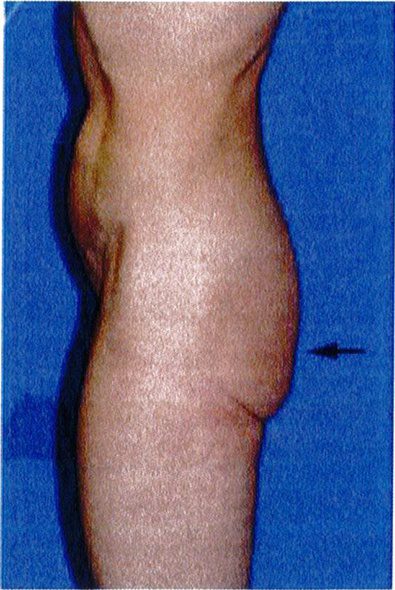

Bước cuối cùng khi đánh giá vùng mông là đánh giá tình trạng sa mông. Đế đánh giá, nên đứng ỏ phía bên để nhìn và phân loại sa mông (từ không sa đến có sa), cả 2 loại này đều được phân loại thành 3 phân lớp phía dưới chúng. Việc phân loại này quyết định xem nên thực hiện quy trình nào cho bệnh nhân.

Phân loại sa mông

Phân loại này được áp dụng khi có vùng da sa xuống dưới nếp lắn mông và chúng được chia thành 3 giai đoạn I, II, III (Hình 28).

GĐ I rất giống với phân loại không sa – lớp C; tuy nhiên, một phần thể tích mông và da sa xuống dưới nếp lằn mông (mức độ ít). Khi nhìn nghiêng, sẽ phát hiện 1 nếp lằn rõ nằm ngang. Trong những trường hợp này, chỉ cần làm đầy mông mà không cần nâng mông trên.

(Hình 28). Ở đây cũng có thể xuất hiện tình trạng mất đàn hồi da và xuất hiện các vết rạn da. Nếu các vết rạn xuất hiện ở khu vực điểm B và C thì nên chỉ định nâng mông; tuy nhiên, đa số trường hợp giai đoạn II chỉ cần làm đầy mông là đủ. Những bệnh nhân này cũng có thể phải cắt bỏ phần da thừa ở gần nếp lẵn mông. Nhưng tác giả khu- yến nghị là nên thực hiện làm đầy mông trước và sau đó đợi từ 3 tới 6 tháng để xem liệu có cần cắt bỏ vùng da thừa đó hay không.

Giai đoạn II

Bệnh nhân ở giai đoạn II, nếp lằn mông vẫn còn nhìn thấy nhưng có tổ chức da sa xuống dưới nếp lắn. Trong khi nếp lắn mông ở giai đoạn I còn nằm ngang thì giai đoạn Il có góc cạnh hơn. Cụ thể, thường có một độ lõm nhất định ở phần trên của vùng mông dưới

Bệnh nhân ở giai đoạn này có phần da chùng nhiều nhất, xuống dưới nếp lằn mông khi nhìn từ phía

của từng đơn vị thẩm mỹ vùng mông sẽ giúp xác định những khu vực nào cần làm đầy/hút mỡ/cắt bỏ hoặc đặt đường rạch.

bên. Nếp lằn này mở rộng về phía mặt trong đùi, và góc tạo bởi chúng và đường liên mông thường lớn hơn 30°. Giai đoạn này cũng được mô tả bởi chỗ lõm ở phân dưới của khu vực trung tâm (hình 28). Các vết rạn da xuất hiện chủ yếu ở vùng điểm B, và da có độ đàn hồi kém với các vết rạn rải rác. Điều trị bệnh nhân ở giai đoạn này cần thực hiện nâng mông trên, cắt vùng da thừa dưới nếp lằn mông và làm đầy mông. Trong các thủ thuật này, có thể thực hiện 1 trong 3 trước đều được.

Ptosis Grade I 0°-10°: Sa mông GĐ 1 0°-10° Ptosis Grade II 10º-30º Ptosis Grade III 30° or greater: Sa mông GĐ III 30° hoặc hơn

Ptosis Grade II 10°- 30°

Hình. 28. Giai đoạn I, II, III của bệnh nhân có tình trạng sa mông. Ở giai đoạn I, góc tạo bởi nếp da nhỏ hơn 10 độ. Ở giai đoạn II, focs này rơi vào khoảng từ 10- 30 độ. Còn ở giai đoan III, góc tao bởi nếp da lớn hơn 30 đô.